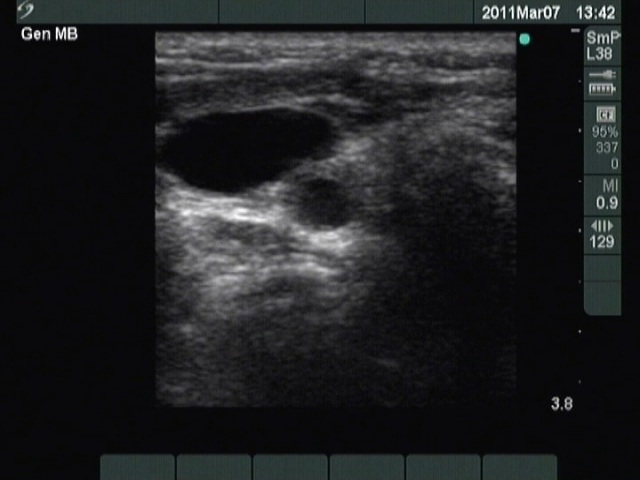

Ultrasound. Except for inconspicuous, moderately hypoechogenic lesion on the ventral wall of the carotid artery, neither thyroid parenchyma in the thyroid beds nor suspicious neck lymph nodes were found. The moderately hypoechoic lesion has bright echogenic granules and was avascular.